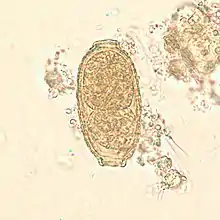

Egg of Paracapillaria philippinensis, formerly called Capillaria philippinensis